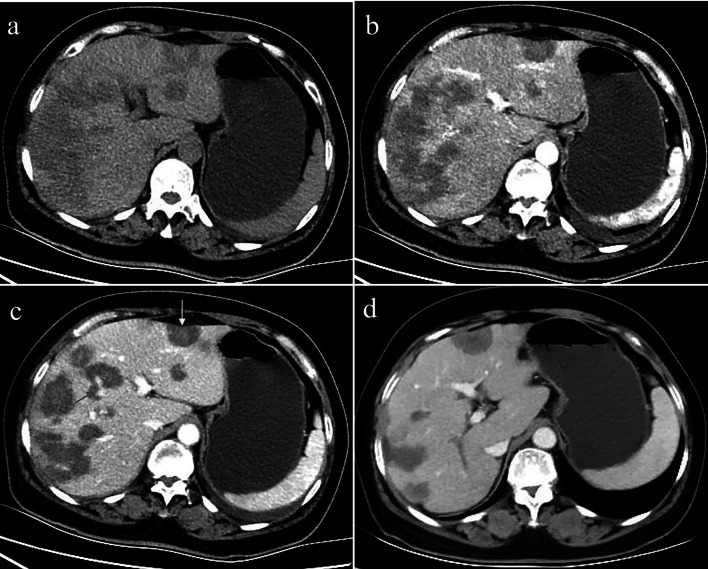

The diffuse type was observed in 8 patients (8/20, 40%). CT features included diffuse low-density lesions with minimal residual areas of normal liver parenchyma, multiple nodules and confluent masses with strip‑like enhancement located at the edge of the liver. Coalescent lesions were detected in most of the cases (7/8, 87.5%). Changes similar to those in liver cirrhosis were detected in 2 patients, such as liver morphological changes, proportion imbalance, and widened hepatic hilar and hepatic fissures (Fig. 4). Multiple lesions displayed slight or ring-like enhancement in the arterial phase and gradual homogeneous or heterogeneous enhancement in the portal phase. One patient showed involvement of lymph nodes; both the peritoneum and lung were invaded in another patient (Fig. 5). Stenosis or occlusion of the branches of the portal and hepatic veins was also detected in 2 patients (Fig. 6).

Fig. 5.

A 34-year-old female with diffuse nodular type HEH. Axial and multiple phase contrast-enhanced CT images (a–c) show multiple, different-sized, coalescing, homogeneous, hypoattenuating nodules diffusing throughout the liver parenchyma. Masses show ring-like enhancement and the “target” sign. At the same time, there was arc-shaped effusion around the liver and peritoneal thickening. Peripheral distribution of masses and capsular retraction are also observed. The axial lung window image (d) shows lung involvement consisting of multiple round-like nodules

Fig. 6.

A 52-year-old female with diffuse nodular type HEH. Axial unenhanced CT images (a) show diffuse coalescing hypoattenuating lesions. Arterial phase CT images (b) show slight enhancement, and some nodules confluent to strip‑like or snowmelt are located subcapsularly in the liver. In the portal phase (c), the lesions are not progressively enhanced, a small branch of the portal vein is seen passing through the middle of the lesions (red arrow), and capsular retraction (yellow arrow). On follow-up CT performed 10 months after radiofrequency ablation, axial portal vein phase CT image (d) shows lesion reduction